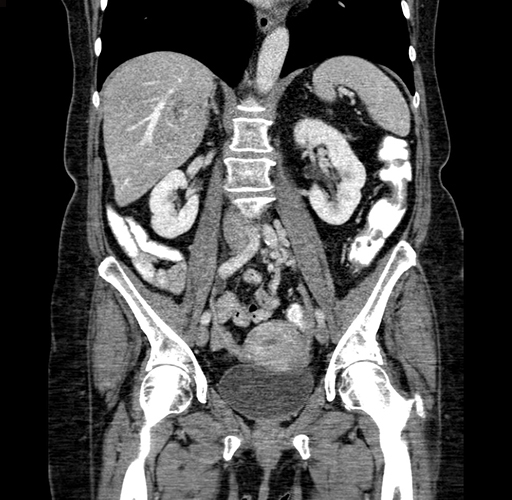

Pre-Chemo: Coronal Venous

Coronal Venous